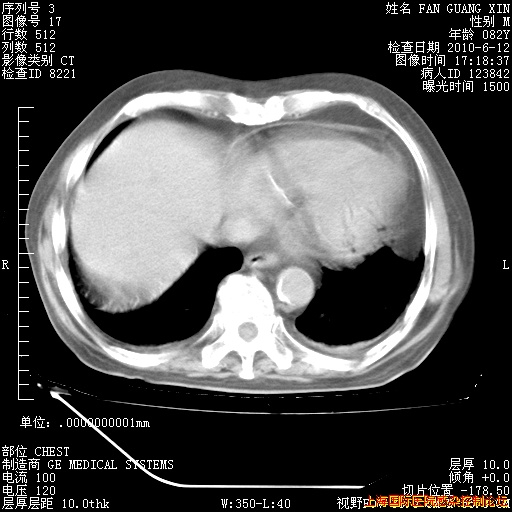

补发6月12日肺部CT肺窗

6月12日肺窗